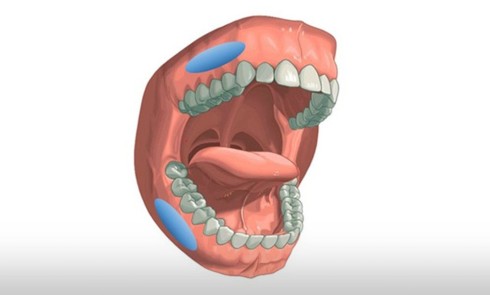

On distingue classiquement trois catégories d’enfants pouvant avoir un Sahos : les enfants sans comorbidités ou pathologies prédisposant au Sahos, les enfants obèses, les enfants ayant une pathologie pouvant être responsable de la survenue ou de l’aggravation d’un Sahos ou encore représentant un facteur de risque opératoire (fig. 1). Sont recherchés chez l’enfant, en plus des symptômes et signes d’une éventuelle maladie sous-jacente ou d’une comorbidité, des symptômes évocateurs nocturnes et diurnes (tableau 2, fig. 2). On retiendra qu’il est exceptionnel pour un enfant :

Selon que l’enfant ait ou non un obstacle ORL, soit âgé ou non de plus de 3 ans, et présente des comorbidités ou des pathologies associées, la démarche d’investigation d’un Sahos clinique n’est pas la même (fig. 3). Cependant, dans tous les cas, cette démarche repose sur l’évaluation précise de l’existence ou non d’un obstacle ORL par un médecin familiarisé à l’examen des enfants.

On évalue également la forme générale des arcades dentaires, les signes d’encombrement, l’occlusion dans les trois dimensions de l’espace ainsi que la posture et la mobilité linguale. Une classe II dentaire marquée, une constriction du maxillaire (endoalvéolie ou endognathie associées ou non à un articulé croisé postérieur) ainsi qu’une béance antérieure sont des signes d’appels de Sahos [8] (fig. 7). Une triade intra-orale évocatrice est souvent présente chez ces enfants : palais étroit et profond, troubles de la posture linguale (macroglossie, frein lingual court, etc.) et Hypertrophie amygdalienne (HTA) [5].

Principe de la prise en charge thérapeutique du Sahos de l’enfant

L’orthodontiste joue un rôle essentiel de dépistage, parfois avant même d’autres intervenants de l’équipe médicale. Il est admis que l’apparition de signes cliniques, notamment nocturnes, est un indicateur pour débuter les thérapeutiques orthodontiques, quand elles sont indiquées, afin d’améliorer la qualité du sommeil et la perméabilité des VAS [19-22]. La morphologie cranio-faciale détermine également le moment du traitement orthodontique : une endognathie maxillaire ou une rétrognathie mandibulaire nécessitent un traitement orthopédique précoce afin de modifier la direction de la croissance et de permettre au squelette cranio-facial d’exprimer son potentiel de croissance [7-23-24].